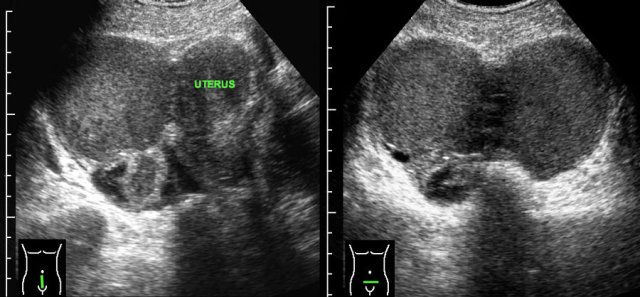

PID case 3

Young woman with acute RLQ pain and a CRP of 140.

Abdominal US was completely normal.

TVUS showed subtle hyperemia of both tubes and ovaries,

surrounded by hyperechoic, moderately compressible, fatty tissue (*).

This

represents slightly inflamed peritoneal, mesenterial and omental fatty tissue.

CT confirmed a normal appendix (arrows) and subtle diffuse hyperdensity of the peritoneal, mesenterial and omental fat (*).

She quickly recovered with antibiotics. Cultures and PCR remained negative.